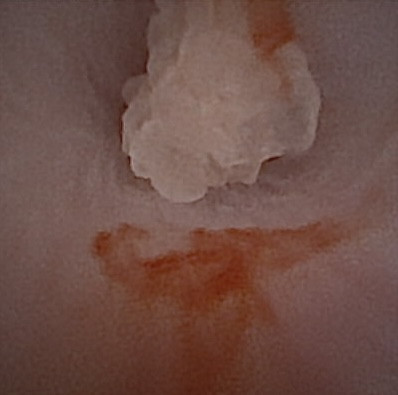

Nous présentons également un cas d'extension d'une rhino-sinusite infectieuse chez un chat présentant une ataxie. Un scanner montre des lésions naso-sinusales agressives avec lyse de la paroi sinusale frontale et empyème méningé adjacent. Une trépanation du sinus frontal permet de réaliser des prélèvements pour analyses bactériologiques et mycologiques. Un traitement antibiotique ciblé permet une bonne évolution clinique.